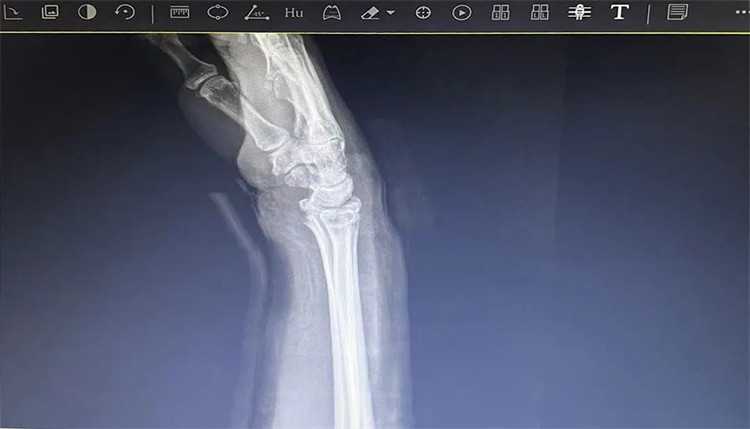

患者老年女性,50多歲,在騎電動(dòng)車停下時(shí)因電動(dòng)車倒下,右手著地,當(dāng)即感覺,右腕及骶尾部腫痛伴右關(guān)節(jié)畸形、活動(dòng)受限,急來我院就診。門診醫(yī)師結(jié)合病史、查體及輔助檢查后,診斷為:右橈尺骨遠(yuǎn)端骨折、骶尾部挫傷并收入住院部。

患者入院后,中醫(yī)正骨科副主任鄭斌斌,認(rèn)真查體及分析檢查結(jié)果后,考慮患者老年女性,建議患者采用拔伸牽引、端提、捺正等閉合手法復(fù)位后,行夾板固定,多能獲得較好療效?;颊邚?fù)位固定后,疼痛明顯減輕。避免了手術(shù)帶來的痛苦及手術(shù)開刀所需費(fèi)用。